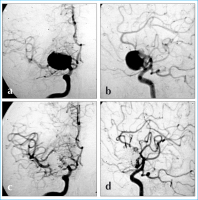

Filmsequenz zu Abbildung 4a-d: Coil-Embolisation Coil-Embolisation. Angiogramme der A. carotis interna in a.p. und seitlicher Projektion (a, b) vor und (c, d) nach endovaskulärer Therapie eines rupturierten Mediabifurkationsaneurysmas rechts. |